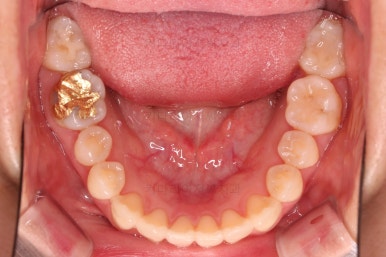

1. 초진

초진 시 입안의 모습입니다.

덧니가 눈에 띄고요.

맞물림이 긴밀하지 못한 상태였습니다.

전반적으로 약간 삐뚤지만 많이 심하다고 보긴 힘들었습니다.

덧니가 있는 방향으로 치열들이 쏠리고 틀어져 중앙선이 맞지 않는 양상이었습니다.